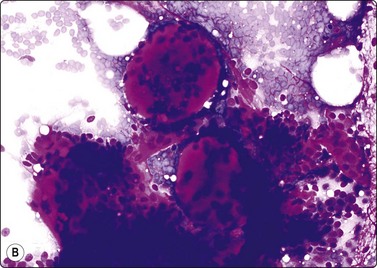

image image

Fig. 8.33 Carcinoid tumor

(A) Plexiform aggregate of small blood vessels with adherent tumor cells (Pap, LP); (B) Aggregate of small regular cells with stippled neuroendocrine nuclear chromatin pattern (Pap, HP).

image

Fig. 8.34 Carcinoid tumor

Dispersed regular tumor cells in company with small capillary blood vessels (H&E, HP).

image image image

Fig. 8.35 Carcinoid tumor, spindle cell type

Tight aggregate of spindle cells with little pleomorphism. Cell block showing no mitotic activity or necrosis. Strong positive immunostaining for synaptophysin (A, H&E, HP; B, Cell block, H&E, HP; C, Cell block, IPOX, HP).

In ‘classic’ carcinoid tumors, the FNB findings are often distinctive enough to permit diagnosis, with or without ancillary tests such as immunocytochemistry. In contrast, the atypical carcinoids that we have seen were more difficult to classify before resection. Nicholson et al. found similar problems in recognizing a proportion of their neuroendocrine carcinomas, including low- and high-grade tumors, and suggested that ‘attention to the presence of loose cell aggregates in a background of singly dispersed cells; feathery patterns created by tumor cells clinging to capillaries; rosette formations; delicate, granular cytoplasm; inconspicuous nucleoli; molding in high-grade tumors; and, most importantly, speckled or dusty chromatin patterns are useful in identifying neuroendocrine differentiation in cytologic specimens’.36